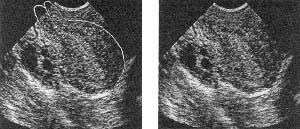

Рис. 19 а, б. Ригидность шеечно-перешеечного отдела. Наполнение мочевого пузыря не устраняет передний перегиб матки, шейка матки при этом отклоняется кзади. Условия для ПЭ ухудшаются.